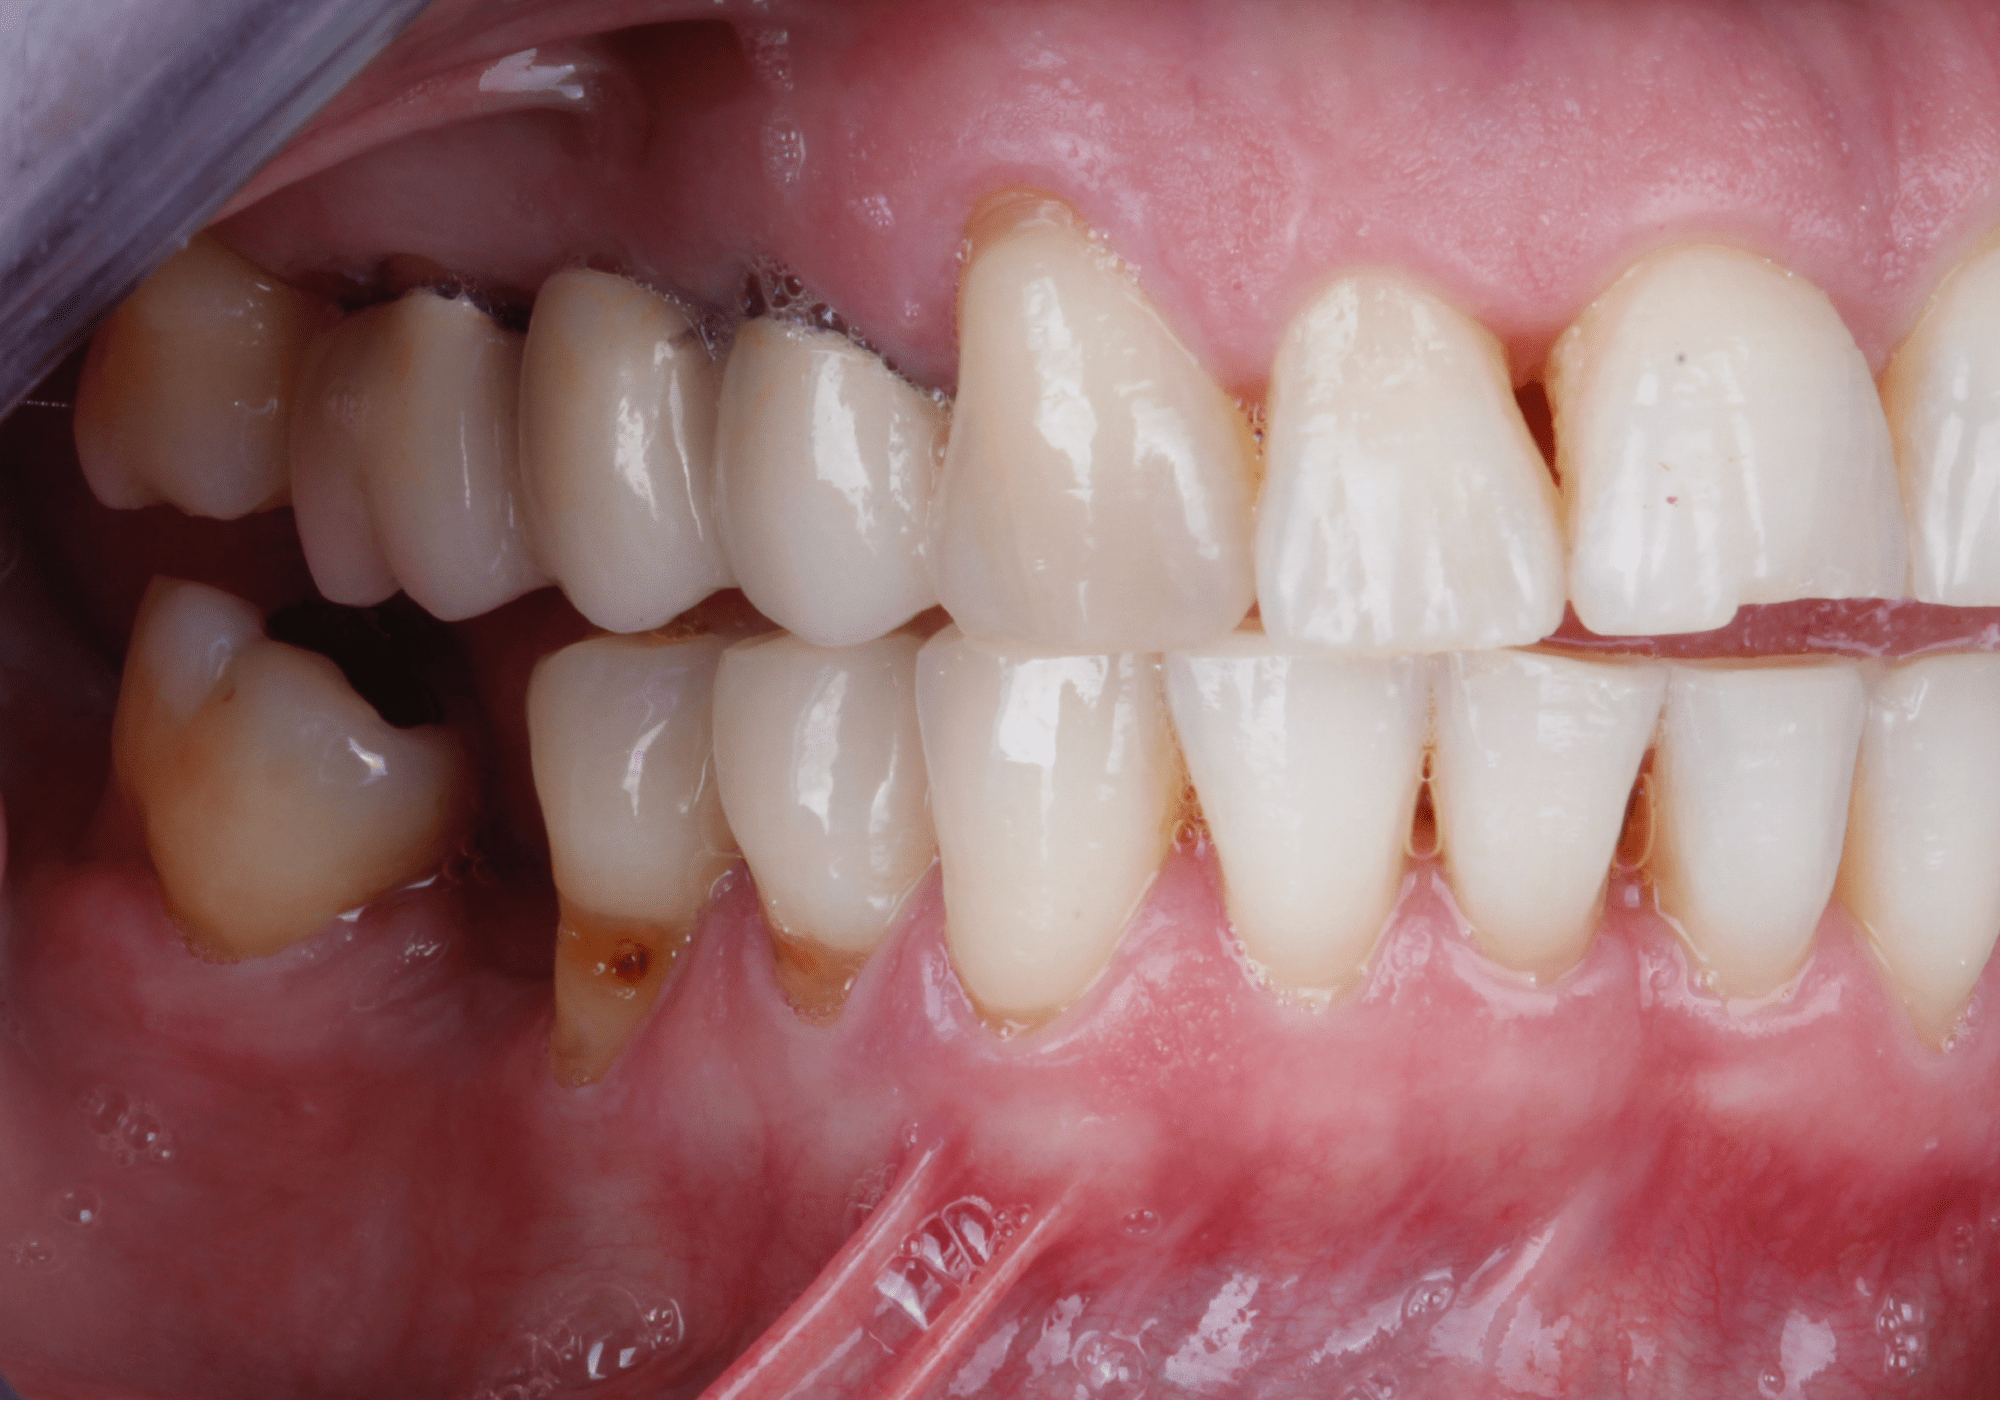

La examinación clínica reveló recesiones en múltiples órganos dentales y dos brechas edéntulas en la mandíbula correspondientes a los órganos dentales “36” y “46” las cuales fueron perdidas debido a caries (Fig. 2 y 3).

También se pudo apreciar que la paciente presentaba un fenotipo delgado y al medir la cantidad de encía queratinizada se observo una banda angosta de la misma, aproximadamente de 1 – 2 mm. (Fig. 4).

Fig. 2

Fig. 3

Fig. 4